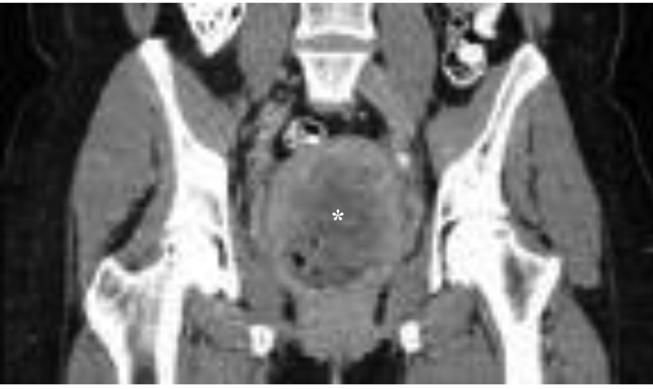

Abstract

We report a case of right-sided leiomyosarcoma of the kidney with concomitant poorly differentiated squamous cell carcinoma of the cervix diagnosed one month after radical nephrectomy in a previously healthy female patient. This is the first reported case of concomitant leiomyosarcoma of the kidney and squamous cell carcinoma of the cervix, and the diagnosis, clinical presentation, prognosis, and treatment are discussed.

我们报告一例右侧肾平滑肌肉瘤合并宫颈低分化鳞状细胞癌的病例。该病例为一名既往健康的女性患者,在根治性肾切除术后一个月被诊断出患有上述疾病。这是首例报告的肾平滑肌肉瘤合并宫颈鳞状细胞癌的病例,并对其诊断、临床表现、预后及治疗进行了讨论。